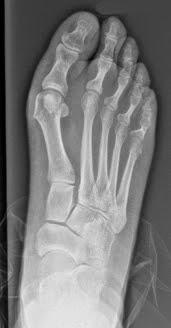

La solución es realizar osteotomías correctoras de la deformidad con lo que se estabiliza el pie y mejora el apoyo.

Creo que el resultado ha sido muy bueno, como se ve en las radiografías que muestro a continuación. Antes y después de la cirugía: